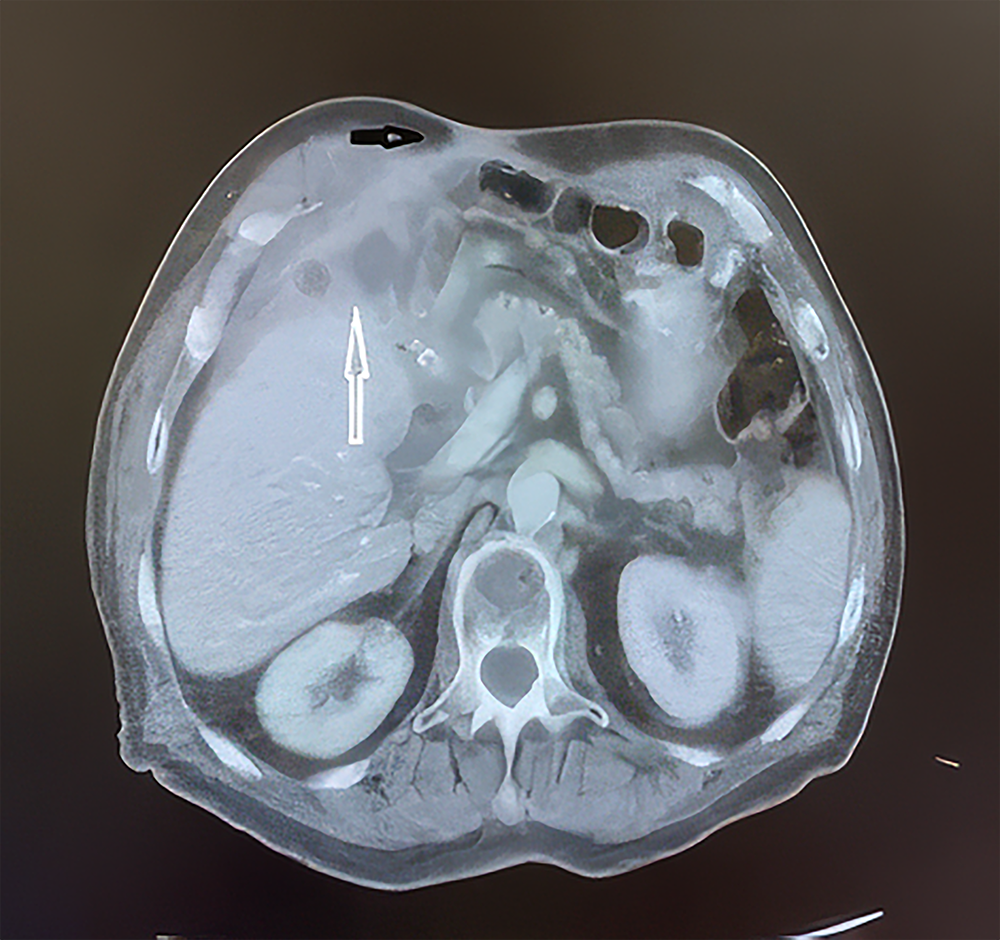

Six months postoperatively, the patient presented with abdominal discharge. Diagnostic evaluation, including abdominal computed tomography (CT), revealed a perihepatic abscess and enterocutaneous fistula secondary to DSL (Figure 1). As the abscess and fistula were localized without systemic complications, conservative management was initiated. Therapeutic abscess drainage was performed using a 12F catheter under ultrasound guidance, accompanied by parenteral nutrition and intravenous antibiotic therapy. Following a reduction in fluid collection, confirmed by ultrasonography, the catheter was removed, and the fistula was repaired. The patient was discharged in stable condition on day 28 and scheduled for a follow-up one month later, where no complaints or abscess recurrence were noted on ultrasonographic evaluation.

Figure 1. A section from the patient’s abdominal CT scan, black arrow: enterocutaneous fistula tract; white arrow: perihepatic abscess formation